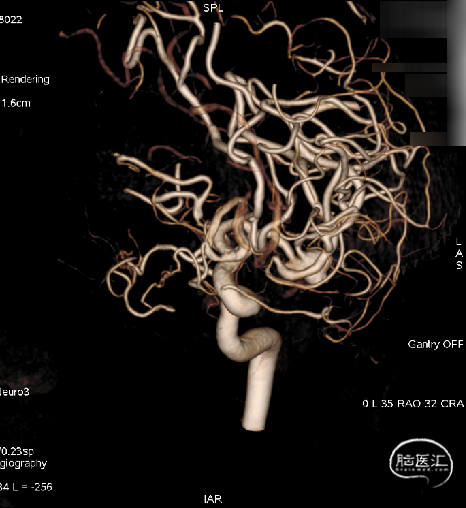

术前影像学检查:术前正侧位。

术前工作位与三维重建:显示右侧MCA分叉部未破裂动脉瘤,6.9mm*7.2mm,瘤颈7.4mm。该病例之困难在于M1迂曲成袢。